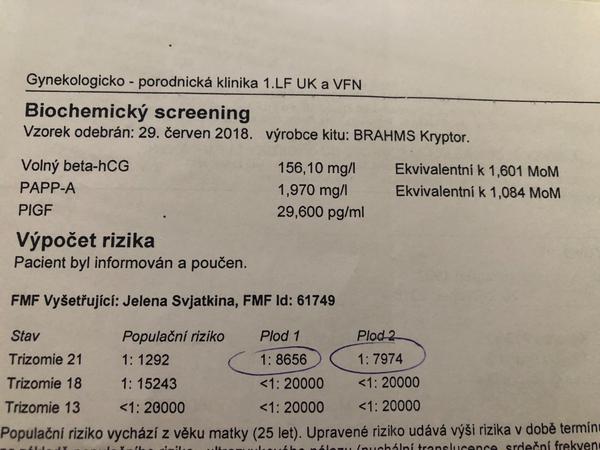

@jednaholkaa No hele, že nekecám. Poslední jsou dvojky.

Ono se to zpřeházelo. Jsou tam vidět datumy.. 🙄

@jednaholkaa Tady jsem schválně našla ty výsledky z předchozích těhotenství 🙂 Obě to jsou holky 🙂 A hodnoty nízké 🙂 Teď zatím hodnoty nevím, na screening jdu ve čtvrtek :D